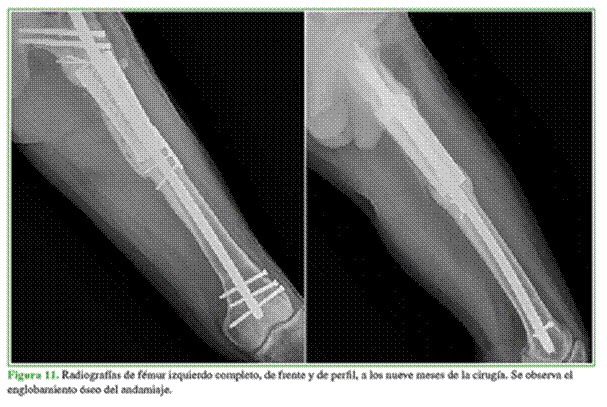

Una vez concluido el tratamiento antibiótico, se realizó una biopsia por punción con rescate negativo. Se procedió a la cirugía reconstructiva (Figura 11).

A los 150 días, se confirma la incorporación ósea completa mediante tomografía computarizada en todos los pacientes. Asimismo, en las radiografías simples, se observa el “englobamiento” óseo del implante, que se considera secundario a la cualidad inductora y la calcificación parcial de la membrana.